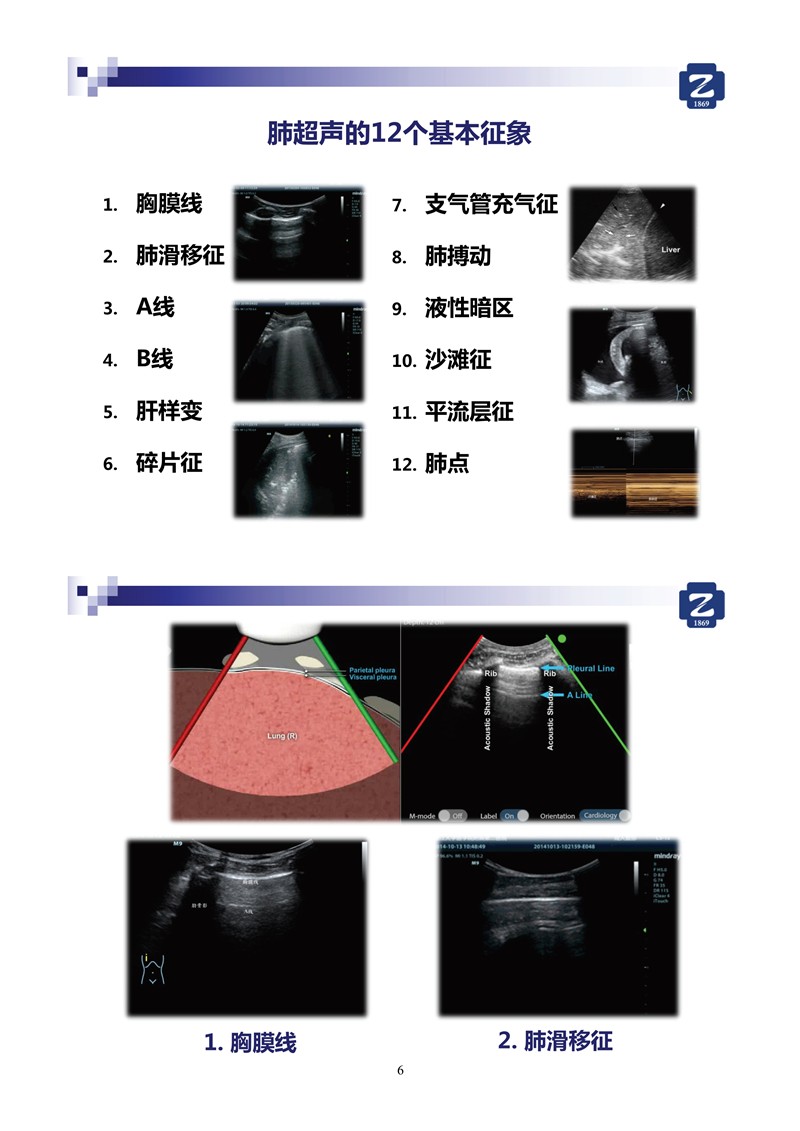

第二版新型冠狀病毒肺炎超聲診斷實(shí)用手冊(cè)_64.jpg